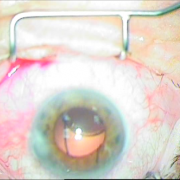

Οι σύγχρονες μικροχειρουργικές τεχνικές αποβλέπουν στον ελάχιστο τραυματισμό του οφθαλμού και στην τοποθέτηση του τεχνητού ενδοφακού στην φυσική του θέση που είναι ο οπίσθιος θάλαμος. Οι ασθενείς απολαμβάνουν τα πλεονεκτήματα των επεμβάσεων μικρής τομής χωρίς ράμματα, με άμεση αποκατάσταση της όρασης και χωρίς μετεγχειρητικό αστιγματισμό.

Sun Set Syndrome

πίσω από την ίριδα

ζώνης 5 ωρών

φακού